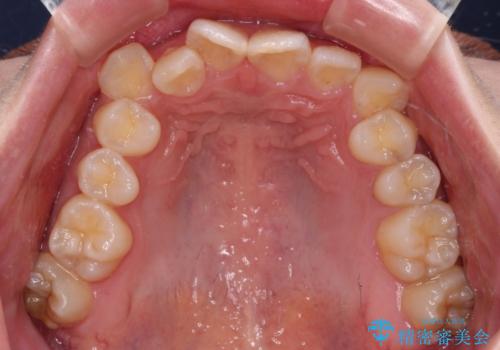

- 上下の八重歯を気にして来院された患者様です。

非抜歯矯正で歯列を整えると、治療後に口元が今よりも突出する可能性が高かったため、上下左右の小臼歯4本を抜歯し、ワイヤー装置にて矯正治療を行うこととしました。

右上の八重歯の影響で、右側は上顎歯列が前方位の咬み合わせとなってしまっていたため、上顎は第一小臼歯を、下顎は第二小臼歯を抜歯することで咬み合わせや上下正中を調整することとしました。